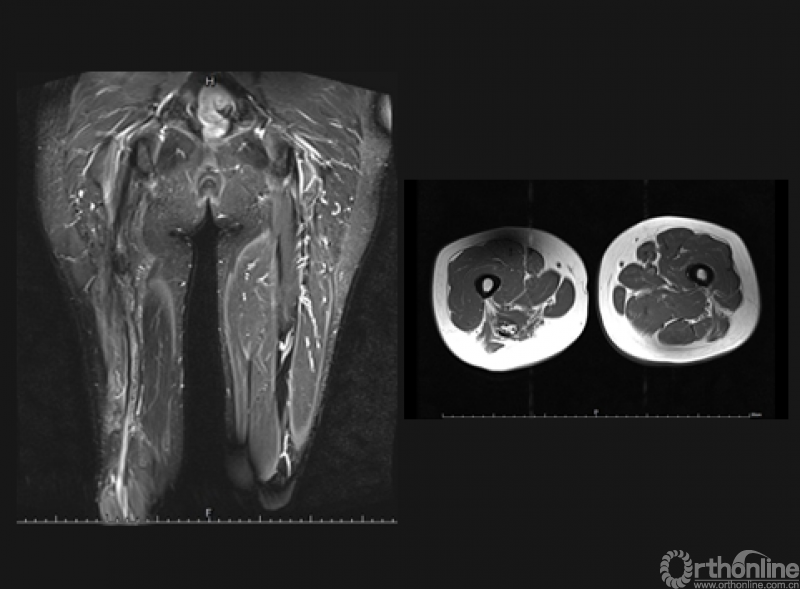

术前磁共振提示肿瘤包绕坐骨神经,周围肌肉组织行R0切除,坐骨神经R2切除边界后行三明治隔离手术,术后随访28月未见复发。

术后磁共振影像